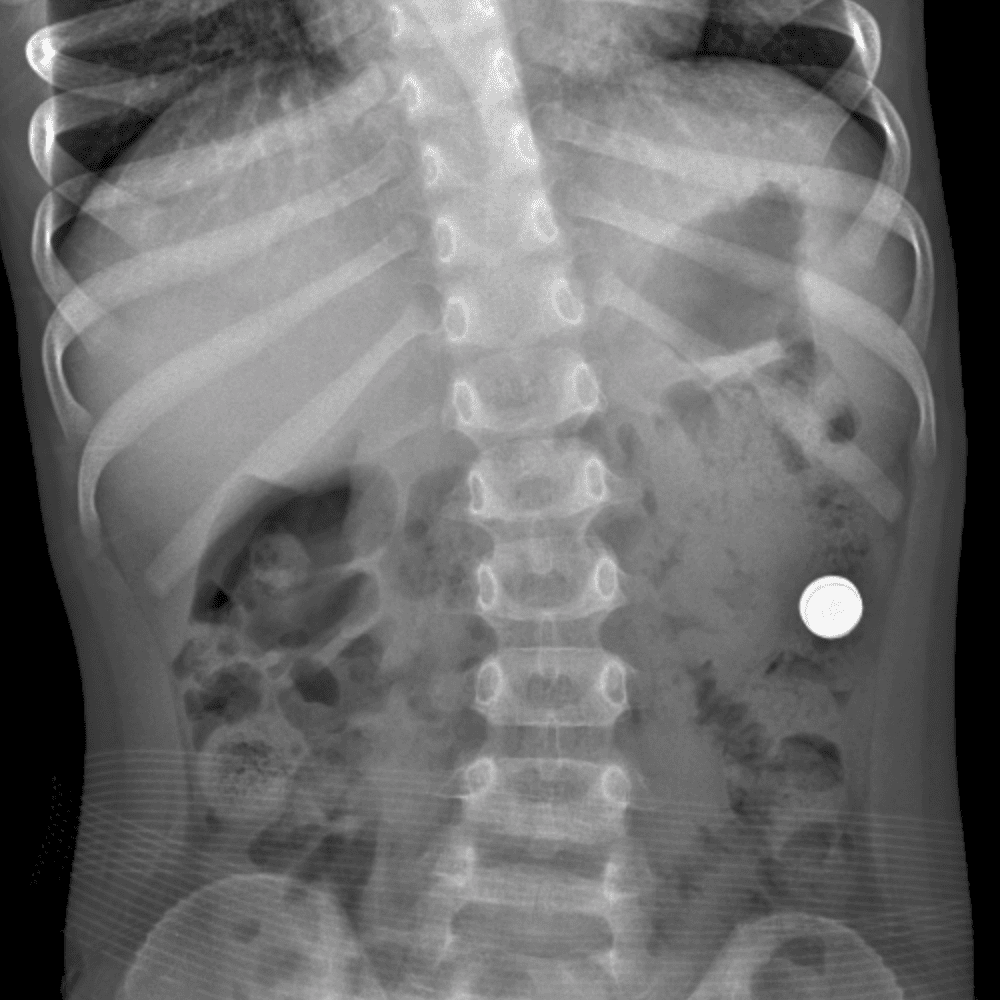

Peds Abdomen

Practice

Simulates call by including subtle or difficult cases and some normals.

30 cases